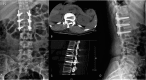

Interventions: The patient underwent PPSF at the level of T12 to L2, but her neurological function did not fully recover after the operation. One week after the injury, we performed TESCD on her.

Outcomes: There was an immediate improvement in her neurological function in just 1 day after 2-stage operation. During the 6-month follow-up period, her neurological functions gradually recovered, and she was able to defecate and urinate. At the last follow-up visit, her spinal cord function was assessed to be at Frankel grade D.